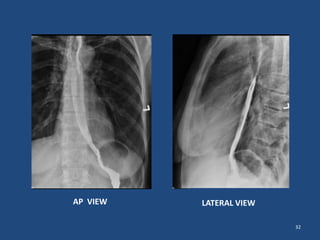

DOUBLE CONTRAST

• Effervescent powder is added to the Ba mixture

250% w/v

• Inj buscopan i.v may be given to keep esophagus

distended for a longer time

• FILMS

1. Control film

2. Spot films- AP/Lateral views of upper, mid & lower

oesophagus

32

AP VIEW LATERAL VIEW